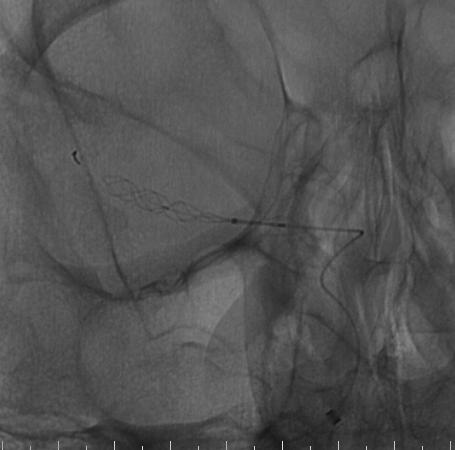

手术过程

右侧桡动脉穿刺置入6F 泰尔茂薄壁鞘,Cat5中间导管同轴rebar27导管头端塑形在0.014微导丝引导下引至右侧颈内动脉海绵窦段,Cat5中间导管引入V18导丝加强系统支撑。

什么达医畅疗·第二期 | 畅医达(Choydar)17小系统血流导向装置经桡治疗大脑中动脉动脉瘤_https://www.jmylbn.com_新闻资讯_第17张